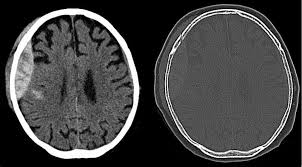

A CT scan of the head is used to confirm the diagnosis. It can show:

The extradural bleed

Any skull fractures